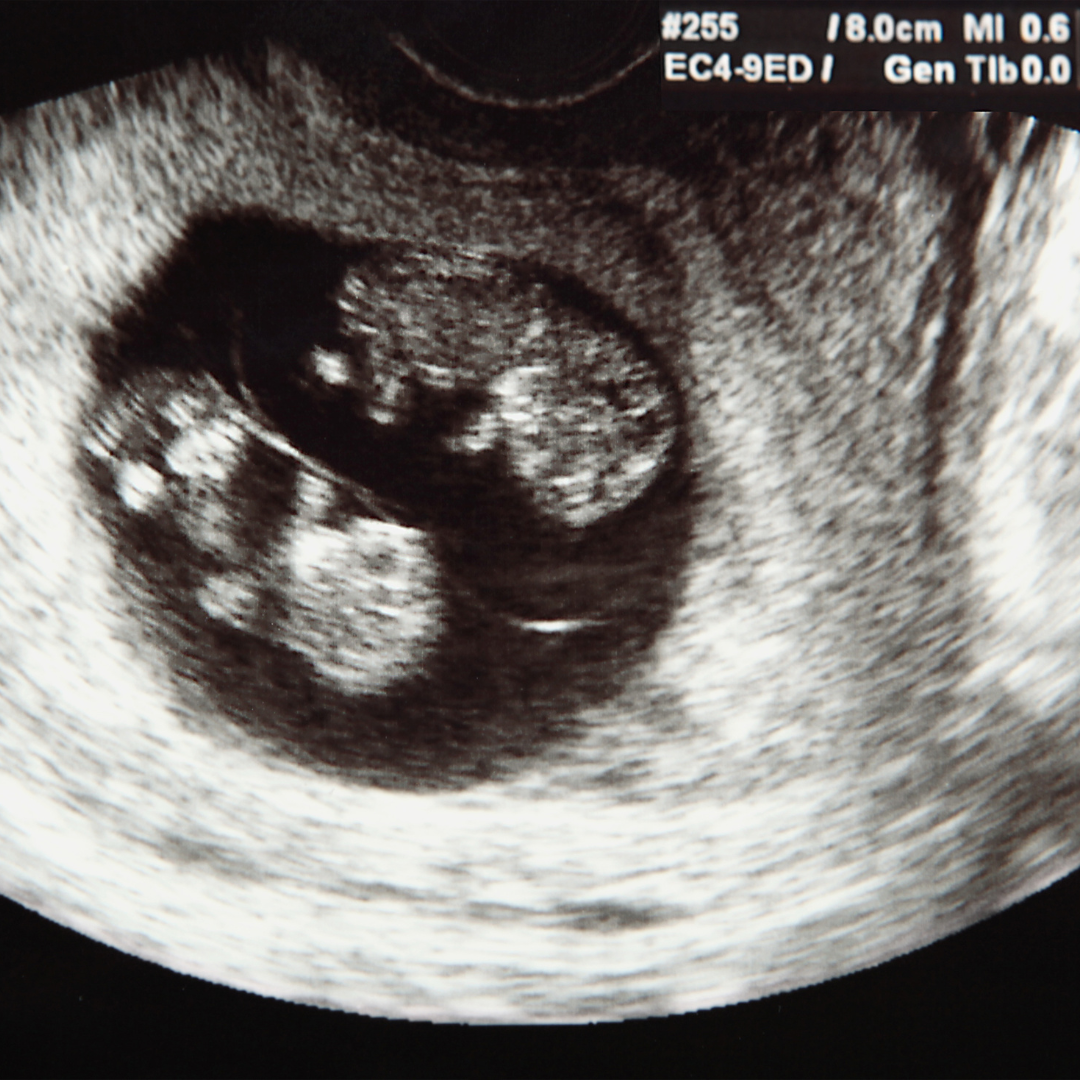

o Pemantauan secara berkala: tes darah (β-hCG), USG untuk melihat implantasi dan perkembangan embrio, serta identifikasi apakah kehamilan kembar atau satu.